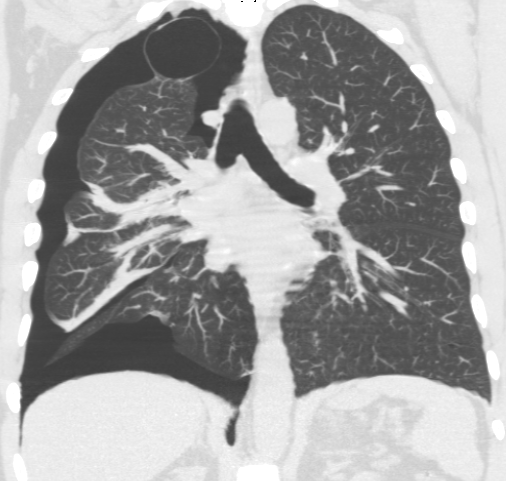

흉부 방사선 사진 촬영으로 진단할 수 있다. 흉부 X선 검사에서 혈관 음영을 동반하지 않는 허탈된 영역은 기흉으로 의심된다.[72] 최대 흡기(숨을 참음) 중에 촬영한 일반 흉부 방사선 사진이 가장 적절한 첫 번째 검사이다.[30] 만기 중에 정기적으로 촬영하는 것은 이점이 없을 것으로 여겨지나,[31] 임상적 의심이 높지만 흡기 방사선 사진이 정상으로 보이는 경우 기흉을 감지하는 데 유용할 수 있다.[32]

흉부 CT을 통해 비교적 큰 낭포라면 위치를 확인할 수 있다.[72] 폐기포를 정확히 확인하기 위해 흉부 CT를 실시한다.[15] CT 스캔은 기흉의 크기를 보다 정확하게 결정할 수 있지만, 이 상황에서 루틴하게 사용하는 것은 권장되지 않는다.[33]